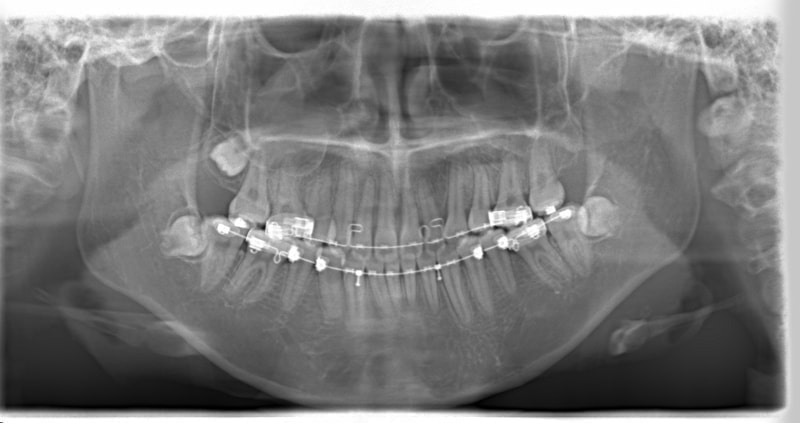

左上3番埋伏歯

治療法:フルパッシブブラケット:T21

治療後(2年後)